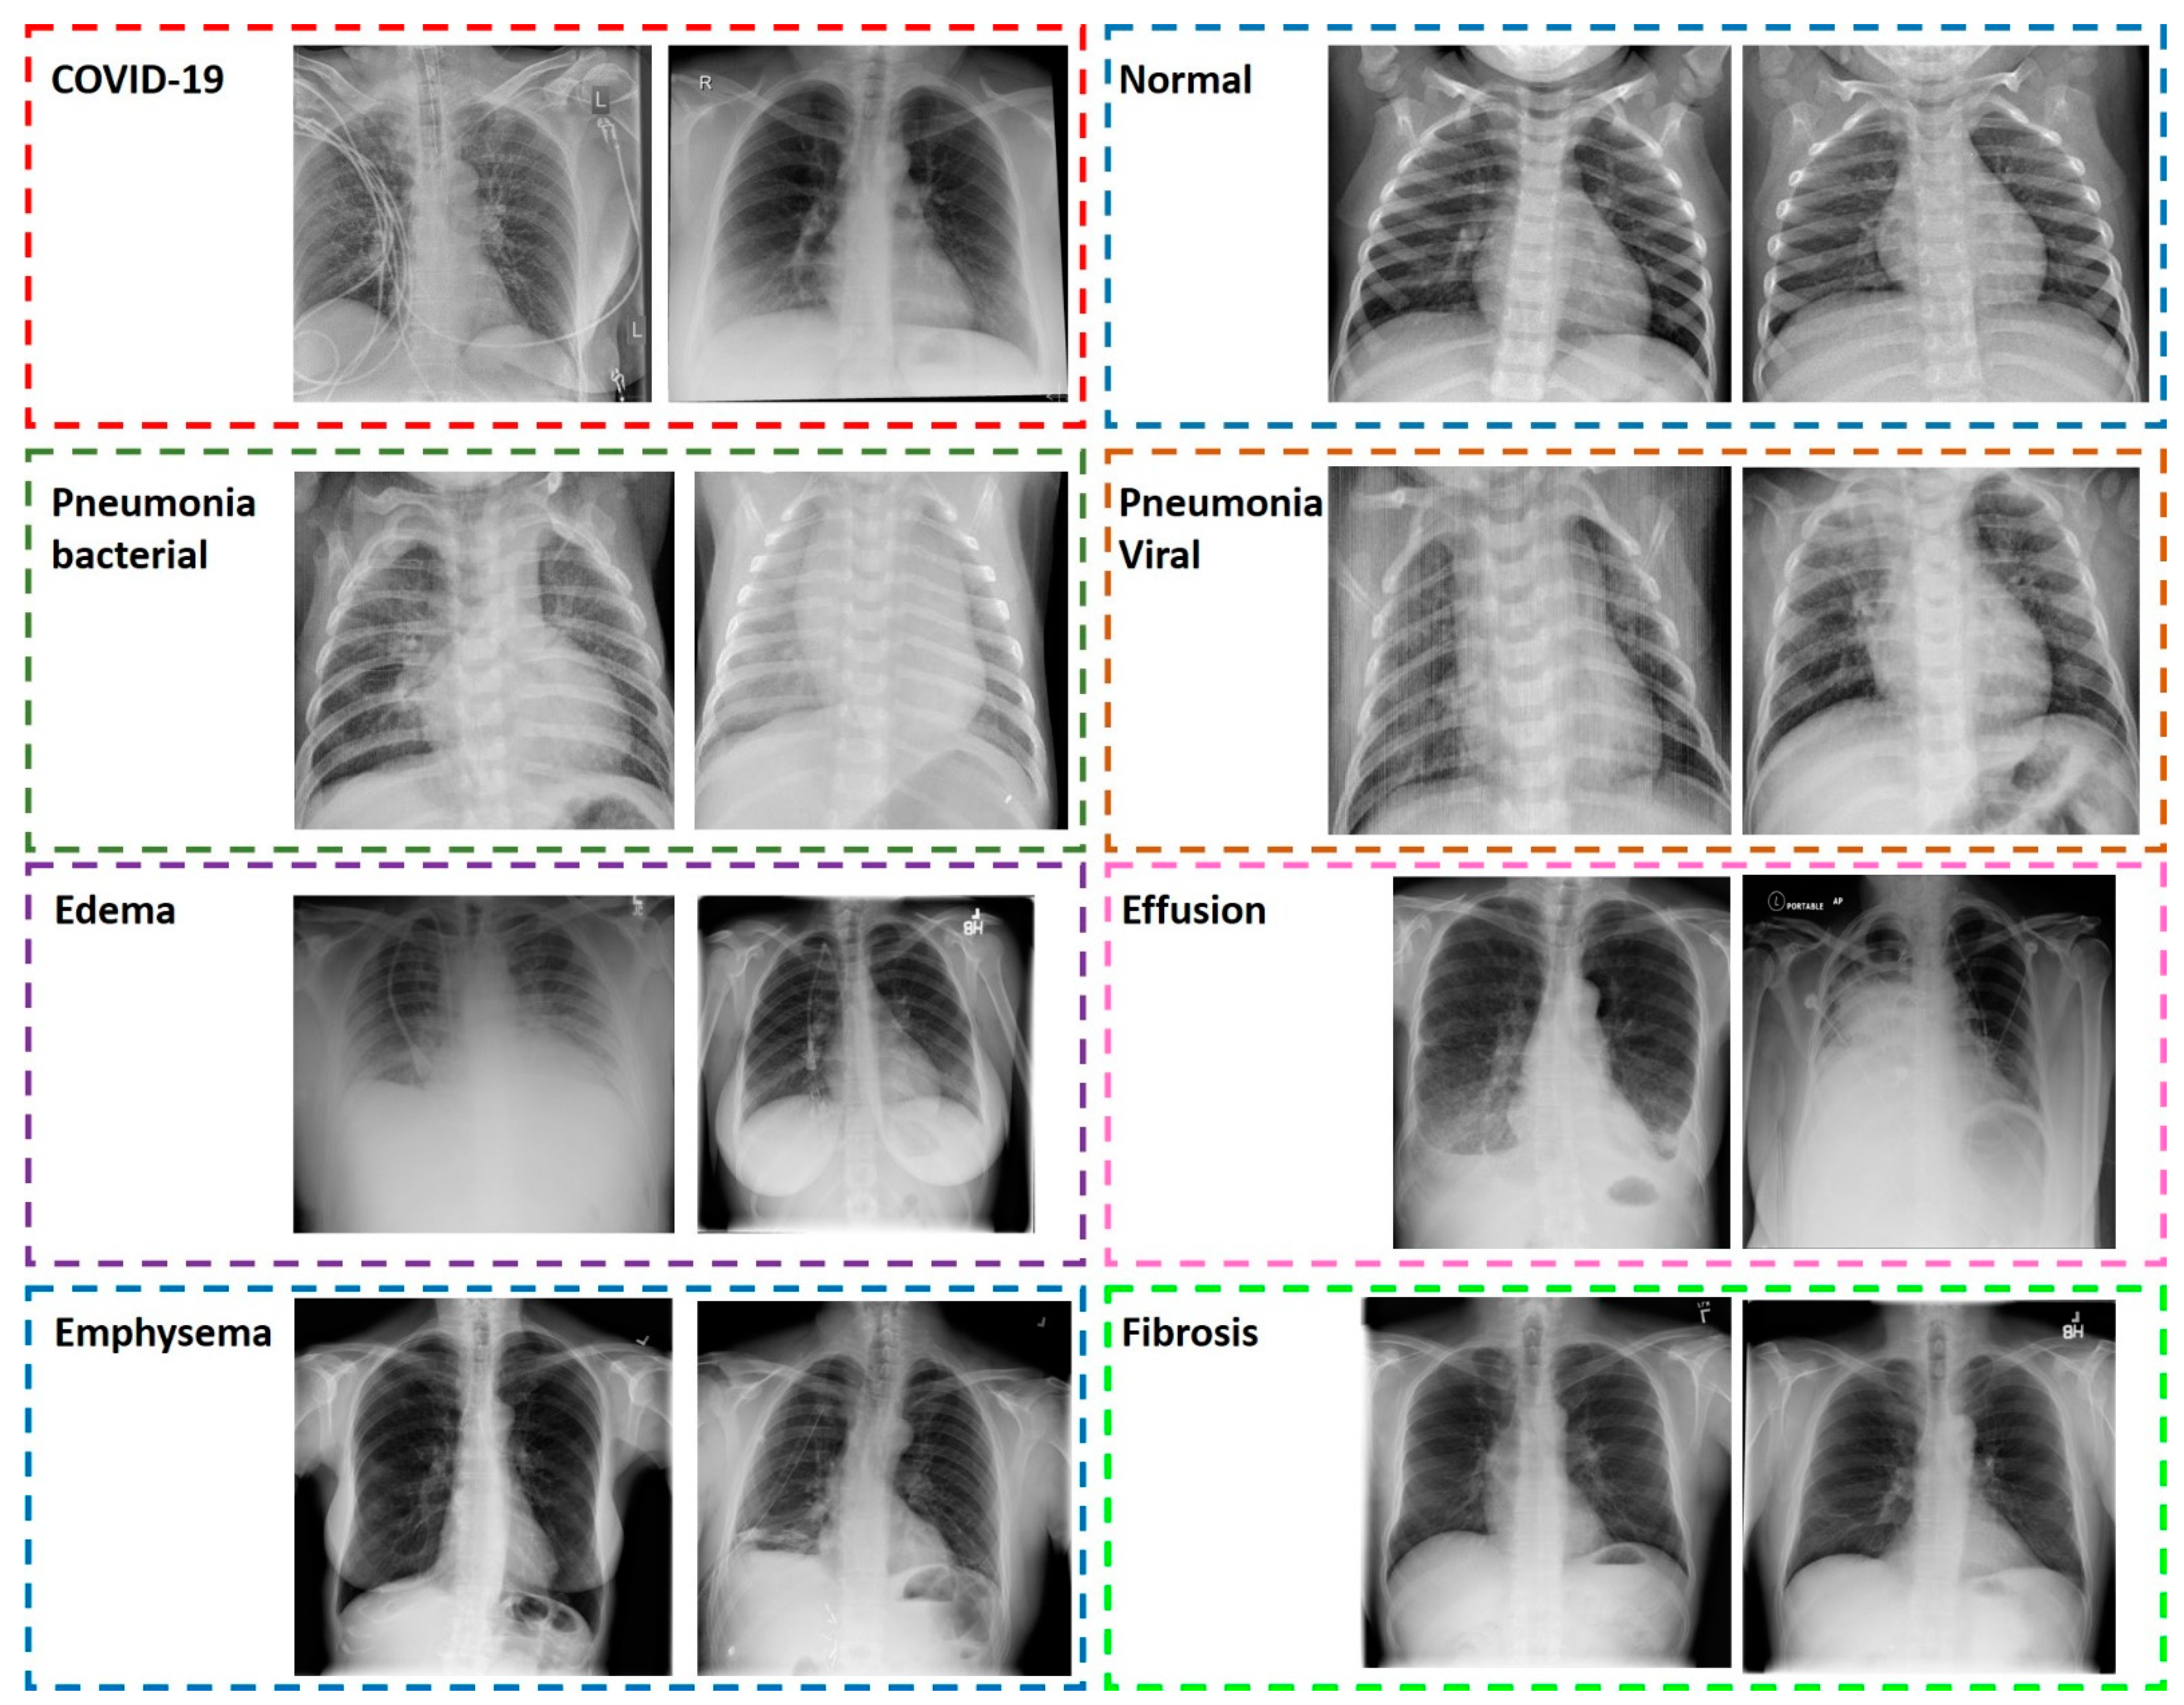

3.2.1. COVID-19, Common Bacterial and Viral Pneumonia X-ray Scans

3.2.2. Pulmonary Diseases Detected from X-ray Scans